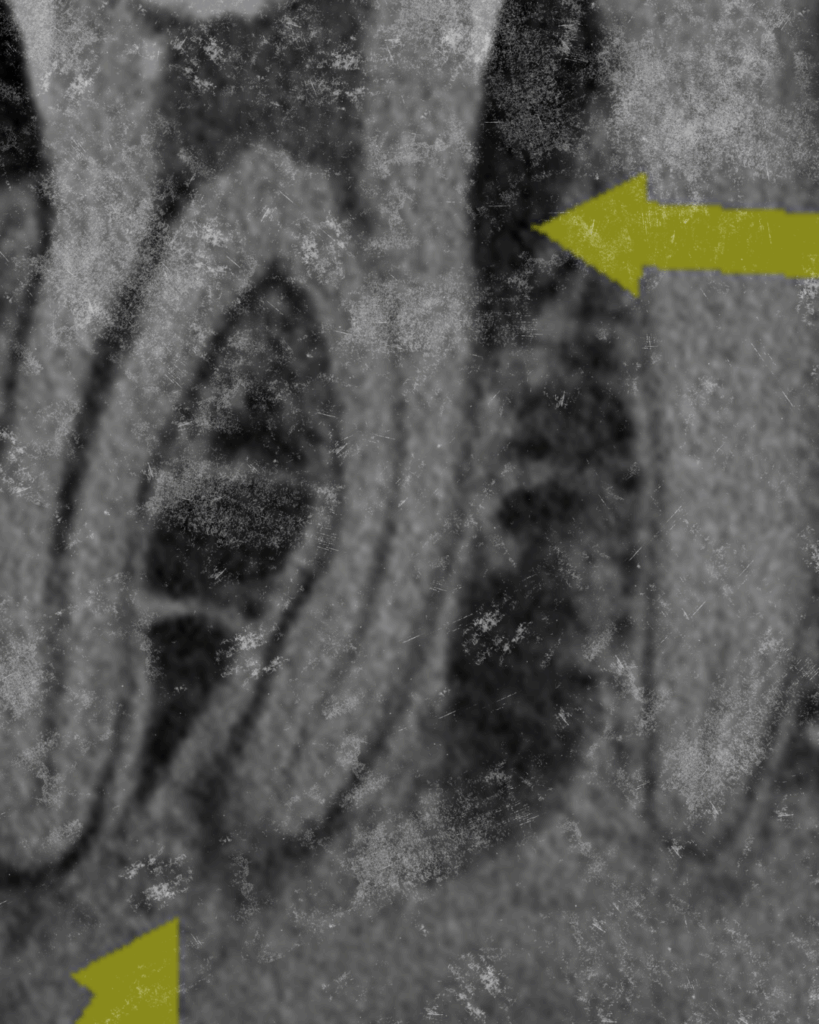

Conventional Endodontic Treatment with 6 year follow-up

When two-dimensional imaging is not enough